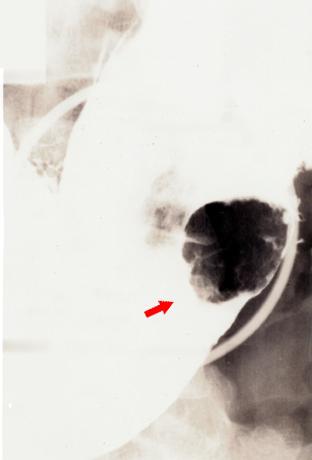

疾病(病理主体)的分类恶性上皮性肿瘤/腺癌

部位(按器官分)胃(部位)/体部

检查方法X线

肿瘤的肉眼分类1型(肿瘤型)/

肿瘤最大直径25~29

肿瘤的深度m